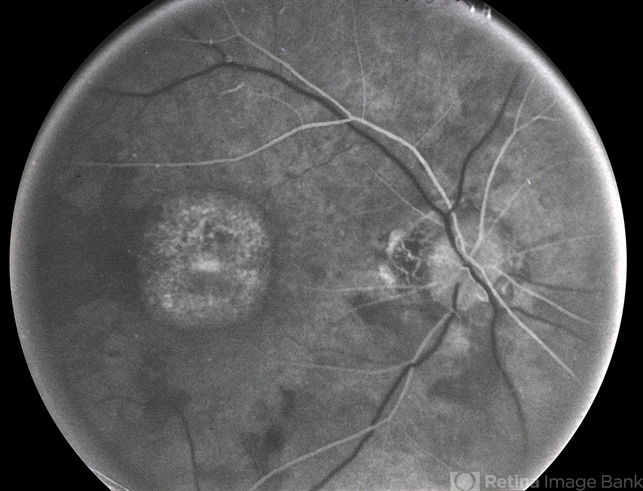

- macular dystrophy

- Macular dystrophy FA.